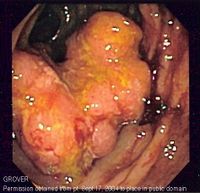

سرطان الشرج ، هو أحد أمراض السرطان والذي يصيب فتحة الشرج ، في نهاية القناة الهضمية. وهو أحد أمراض سرطان القولون. ويعتبر نمو سرطان في فتحة الشرج أو الغشاء المبطن لها هو سرطان غير شائع – ويمثل نسبة صغيرة من الأورام السرطانية للقولون والمستقيم وفتحة الشرج. يكون أكثر شيوعا في الرجال في الجزء الخارجى من فتحة الشرج عكس النساء حيث يكون أكثر في الجزء الداخلي. يجب ملاحظة أن الأورام التى تحدث في الجلد الخارجى حيث يوجد الشعر هى أورام في الجلد وليس فتحة الشرج. [1]